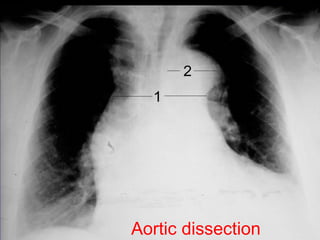

Aortic dissection with hemothorax

Aortic dissection